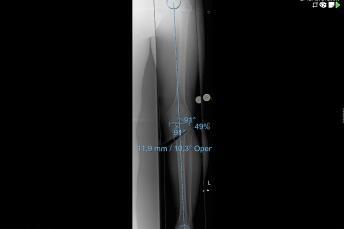

Pathological deformities of the upper or lower leg bones result in incorrect loads on the knee joint, but they can also result in restricted movement. A precise axis analysis, which we can perform with the help of a computer programme, shows us the location of the deformity. This enables us to carry out a correction at the site of the malposition by cutting through the bone (osteotomy) and then stabilise this correction with stable-angle plates. Partial weight-bearing and free mobility is usually possible immediately. Osteotomies close to the knee joint on the upper leg (femur) and lower leg (tibia) have proven successful in the prevention and treatment of osteoarthritis and in the treatment of ligament instabilities.